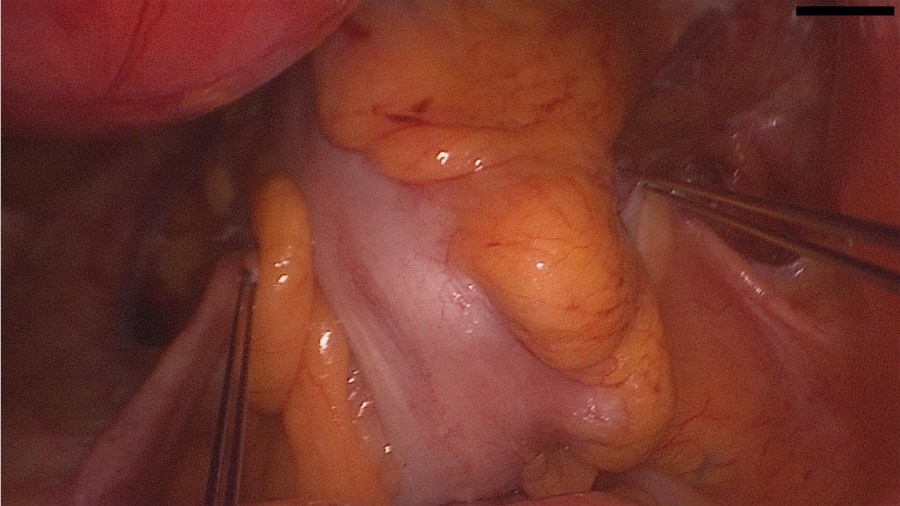

The patient came to us for removal. In our work-up we asked for a preoperative low-dose abdomen CT, which verified intraperitoneal lie of the IUD and excluded bowel involvement.

Interestingly, the patient had experienced the desired amenorrhea for almost 5 years, despite the fact that the IUD was lying inside the greater omentum and not inside the uterus.